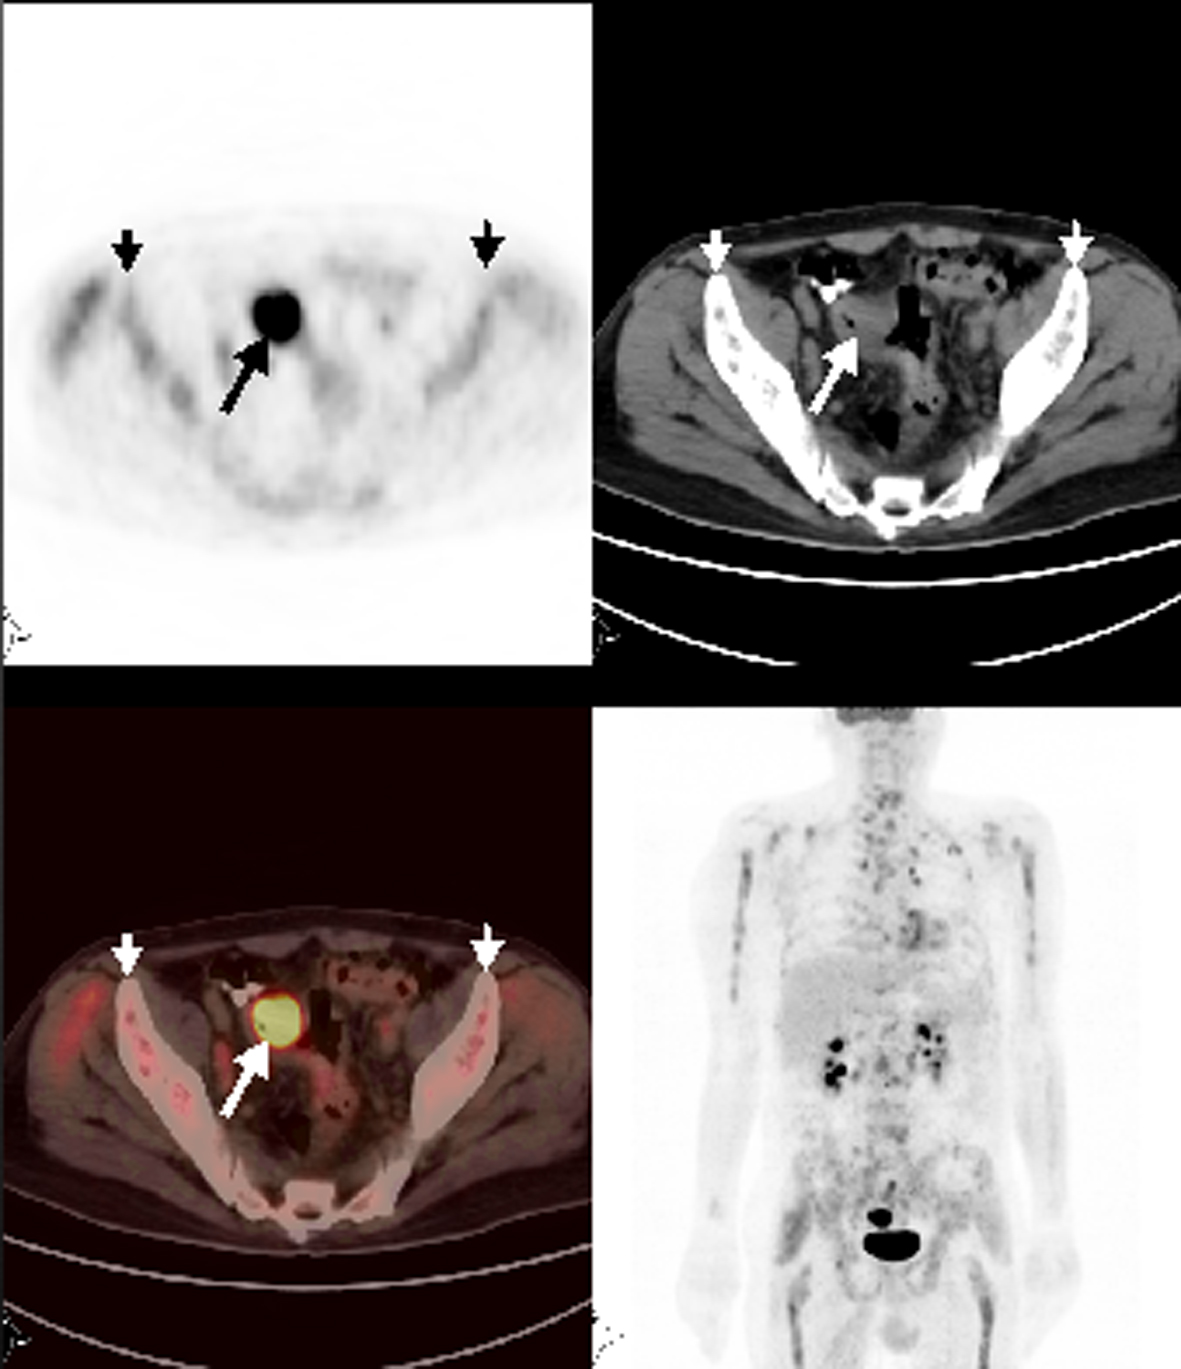

Patient 4

A 67-year-old man with sigmoid colon cancer was referred for PET/CT for the evaluation of increased tumor marker after one year of diagnosis. FDG-PET/CT revealed tumoral wall thickening with intense FDG uptake at the sigmoid colon consistent with recurrence and metastatic mesenteric and paraaortocaval lymph nodes. In addition, there was widespread heterogeneously increased FDG uptake in the skeleton consistent with bone marrow involvement (Fig. 2). Bone marrow biopsy proved mucinous tumor involvement despite a platelet count of 179,000 per µL.

![]() Click for large image | Figure 2. Axial and MIP PET/CT showed a mass with intense FDG uptake at the sigmoid colon consistent with primary tumor. Also, there was heterogeneously increased FDG accumulation at the skeleton suggestive for bone marrow metastases. |